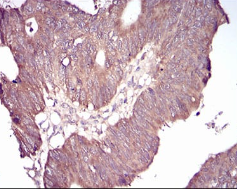

GSK3B Mouse Monoclonal antibody[3D6B4]

AC2395 GSK3B Mouse Monoclonal antibody[3D6B4] 100ug $367 10days

IHC    1/200 - 1/1000